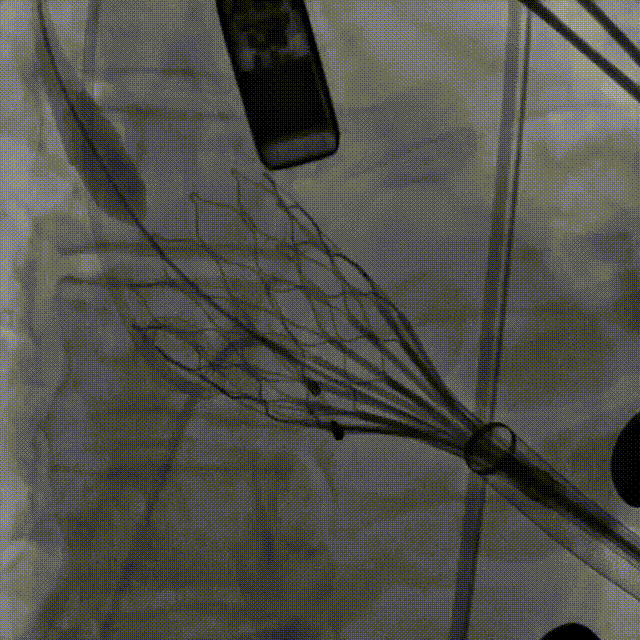

TA32瓣膜,第一次释放

造影观察,瓣膜较深,可见瓣周漏

瓣架打平造影,瓣膜位置偏深,回收

第二次释放

造影观察 瓣膜深度可

稳定脱钩,瓣膜无位移

最终造影,瓣膜位置可,几乎无瓣周漏

本例手术中,患者瓣环直径达29.7mm,且为单纯反流结构,存在瓣膜锚定困难、释放位置要求高等技术挑战。高永生教授团队选用的ScienCrown瓣膜凭借其“全释放/全回收”功能,突破了既往瓣膜部分可回收的操作限制,显著提升了植入过程的调控精度与容错率,从而保障了手术安全。其独特的直筒型设计使瓣膜能够实现多节段锚定,提供更稳固的径向支撑力。本例植入TA32号瓣膜,oversize仅约7.74%,依旧能够提供充足锚定。